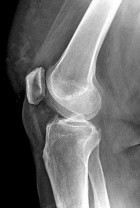

P.P. - 55 year old female c/o right knee pain x 1.5 years. Pain is dull, intermittent, worse with activity. No mechanical symptoms. No history of trauma. Treatment with NSAIDs, aspirations, viscosupplementation, intraarticular steroids provide minimal relief.

Zoom image: Radiological image Radiological image.